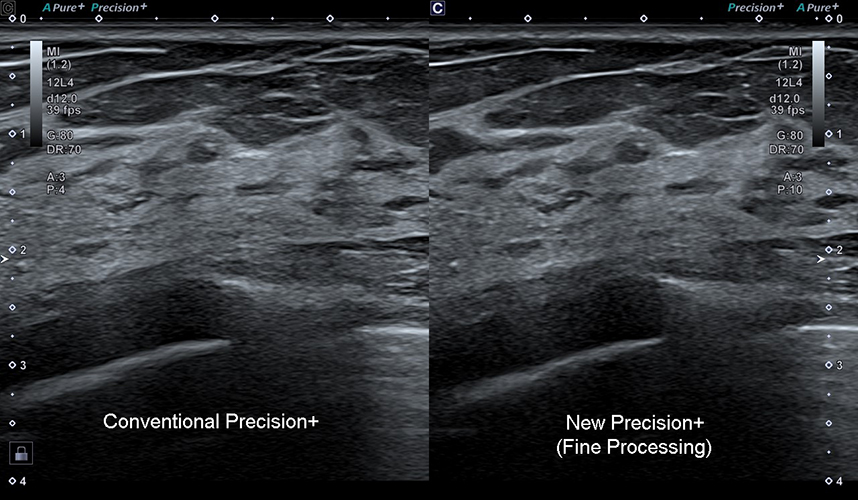

Precision+ Режим точної обробки

Precision+ відомий своєю видатною продуктивністю у створенні однорідних зображень із чіткими контурами, покращеною рівномірністю зображення та зменшенням артефактів. Новий режим Fine Processing Aplio beyond забезпечує ще чистіші зображення з більш чіткими контурами.